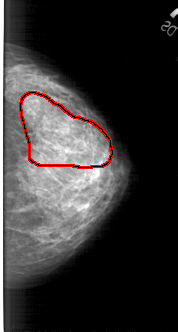

FILE: A_1677_1.RIGHT_CC.OVERLAY

TOTAL_ABNORMALITIES 1

ABNORMALITY 1

LESION_TYPE CALCIFICATION TYPE PLEOMORPHIC DISTRIBUTION SEGMENTAL

ASSESSMENT 4

SUBTLETY 1

PATHOLOGY MALIGNANT

TOTAL_OUTLINES 1

BOUNDARY

RIGHT_CC LINES 4966 PIXELS_PER_LINE 2656 BITS_PER_PIXEL 12 RESOLUTION 43.5 OVERLAY